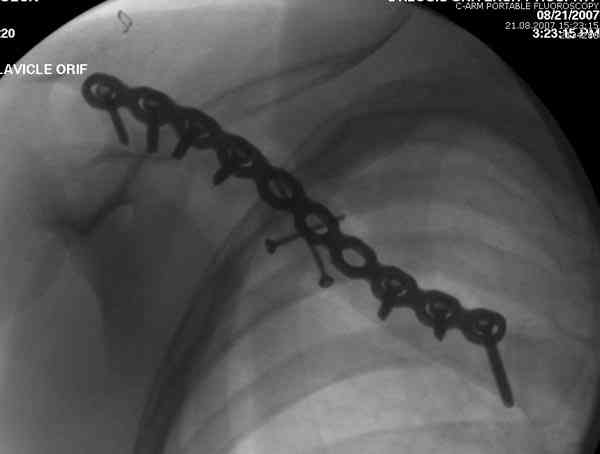

Недавно разбирали случай ложного сустава.

45 летная женщина после автоаварии, алкоголь 163 и 20 летним стажем курения.

Консервативное лечение, через 8 мес. операция Rockwood pin с костной пластикой в нашем городе другим врачом. После 8 недели падение, гвоздь удален оперирующим хирургом, больная направлена к нам. Фиксация реконструктивной пластиной с трикортикальным графтом, добавлен BMP-2. Для стабилизации фиксацию провели через акромион.

Вот уже два месяца больная также продолжает жаловаться на боли, буквально на днях удалили акромиальную часть пластины с специальной пилой с алмазным покрытием для медицинского металла. До сих пор судьба ложного сустава неизвестна....

Второй случай тоже недавно оперирован по поводу

ложного сустава, в марте травма, через 4.5 половиной

операция..